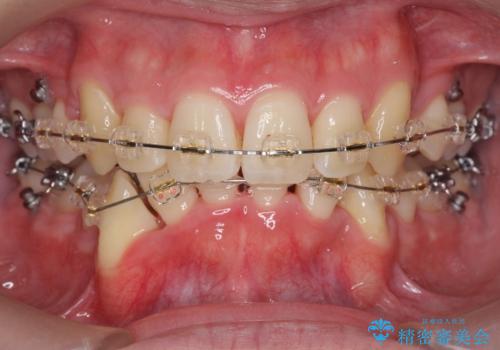

前歯のがたつき 下の八重歯

- 前歯のがたつきを主訴に来院。

上下左右の小臼歯を抜歯しています。

下のがたつきが大きいため、抜いたスペースをしっかり利用して並べるため矯正用インプラントを使用しています。

上下の前歯の重なりが大きく(過蓋咬合)時間がかかりましたが、しっかり浅く仕上げることができました。